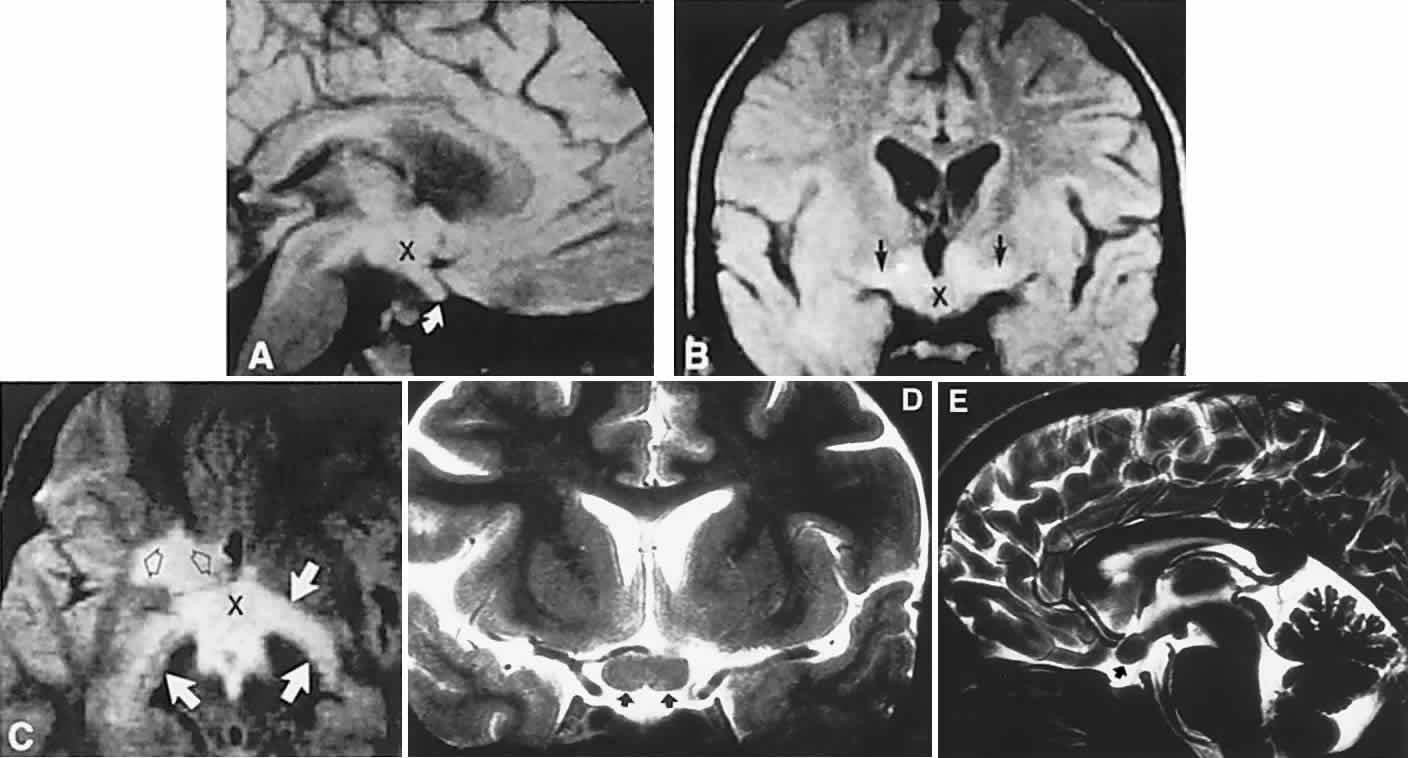

Endocrine-inactive tumors fail to produce clinical manifestations of any secretory product when a normal hormone is produced in amounts too small to be detected, when an abnormal hormone is produced but not recognized by biologic receptor sites or detected by radioimmunoassay, or when formerly endocrine-active cells have lost the ability to produce hormone as a result of degeneration. Of 1000 pituitary tumors surgically treated by Wilson,20 226 were endocrine-inactive, and 774 were secretory, as follows: PRL, 410; GH, 195; ACTH, 167; thyroid-stimulating hormone, 2. Nonsecretory adenomas, which consist mostly of null-cell adenomas, tend to be larger at presentation than do secretory tumors, with a median age of 57 years, and male predominance.21 Nonocular symptoms, as previously discussed, include chronic headaches (severe or mild) in more than two-thirds of patients,1 fatigue, impotence or amenorrhea, sexual hair change, or other signs of gonadal, thyroidal, or adrenal insufficiency. The typical sequence of hormonal deficiencies associated with large adenomas is early loss of GH and gonadotropin, later loss of thyrotropin and corticotropin. With the increasing application of neuroimaging and sensitive assays for abnormal hormones, the incidence of ophthalmologic presentation is decreasing, whereas the incidence of neuro-endocrine findings is increasing. Signs and symptoms, visual or otherwise, nonetheless may exist for months to years before so much as a visual field or plain skull film is obtained.4 Visual failure with pituitary tumors assumes a limited number of field patterns. As suprasellar extension evolves, a single optic nerve may be compromised, with resultant progressive monocular visual loss in the form of a central scotoma. More frequently, as the tumor splays apart the anterior chiasmal notch, superotemporal peripheral hemianopic defects occur. However, this well-touted superior bitemporal hemianopia is almost always accompanied by minor or major hemianopic scotomas approaching the fixational area along the vertical meridian (see Fig. 1). Asymmetry of field defects is the rule, the eye with the greater deficit likely showing diminished visual acuity. Marked asymmetry is not uncommon, such that one eye may be nearly blind while the other shows a temporal hemianopic defect (see Fig. 1C); this combination is as exquisitely localizing to the chiasm as is classic bitemporal hemianopia. Adenomas extending posteriorly produce incongruous hemianopias (see Fig. 5) by optic tract involvement; central vision is usually diminished, at least in the ipsilateral eye, and optic atrophy evolves. On extremely rare occasions, arcuate Bjerrum's scotomas extend from the blind spot into the nasal field22 or terminate at the vertical meridian.23 Such defects are usually monocular and are difficult to distinguish from glaucoma by perimetry alone. With progression, especially if the temporal field of the other eye becomes involved, a more typical field pattern evolves. In late stages of visual loss, the only suggestion of the chiasmal character of field defects may be minimal preservation of the nasal field of one eye (see Fig. 1C). The importance of serial examinations is obvious, but, when doubt exists, neuroimaging is mandatory. The absence of field defects, for example, in patients undergoing evaluation for amenorrhea, galactorrhea, or sellar enlargement incidentally discovered, does not imply the absence of an adenoma. Obviously, patients with microadenomas, that is, confined within the sella, do not have field defects. From a study24 of 50 cases of pituitary adenomas with chiasmal syndrome, it was concluded that visual disturbance occurs when the chiasm is displaced approximately 10 mm upward (see also Volume 2, Chapter 4, Fig. 6). The modern management of pituitary adenomas should involve several disciplines: current neuroradiologic studies detect microadenomas and provide precise delineation of gross morphology and status of neighboring structures, and mixed MRI signals suggest new or old hemorrhage, cysts, and so forth (Fig. 2); radioimmunoassay techniques assay PRL and other endocrine levels; oral neuropharmacologic agents, such as bromergocryptine, provide a “medical adenomectomy” for hyperprolactinemia and acromegaly; transsphenoidal surgery, including high-illumination microscopical procedures, televised radiofluoroscopic monitoring, and infection control, has all but replaced transcranial approaches; immunohistochemistry techniques have replaced the anachronistic tinctorial designations (e.g., chromophobe, basophilic) with a functional classification. PRL-secreting adenomas are the single most common type of pituitary tumor and occur more frequently in women than in men.20 Most of these tumors are microadenomas, although tumors confined to the sella are relatively rare in men. In women, amenorrhea and galactorrhea are the symptoms that provoke investigation, whereas in men, symptoms include loss of libido, impotence, gynecomastia, galactorrhea, and hypopituitarism.25 These various clinical manifestations occur with or without visual loss, depending on the volume of the adenoma; that is, the degree of suprasellar extension and compression of the chiasm. As a rule, true prolactinomas are associated with serum PRL levels higher than 150 to 200 ng/ml, and they usually range from 700 to 7000 ng/ml; the larger the tumor, the greater the serum PRL and, therefore, radiologically large adenomas with PRL levels lower than 200 ng/ml are probably nonsecreting and are not likely to respond to medical therapy (see below). Hyperprolactinemia up to 100 ng/ml may be due to simple physiologic causes, including stress, sexual intercourse, nipple stimulation, and exercise, or it may be secondary to pharmacologic agents such as phenothiazines, tricyclic antidepressants, calcium channel blockers, and cimetidine.25 However, other lesions in and around the pituitary gland and hypothalamus that compromise the pituitary stalk may present as “pseudoprolactinomas.” Immunohistochemical studies performed on 97 tissue specimens in patients operated on for presumed prolactinomas at the Mayo Clinic in Rochester, Minnesota26 revealed 65% to be microadenomas, but null-cell tumors accounted for 4 of 5 pseudoprolactinomas; these tended to be large at diagnosis, but with minor PRL elevation. Suprasellar cystic lesions can also cause hyperprolactinemia with field defects,27 as can carotid suprasellar aneurysms.28 Unlike true prolactinomas, non-PRL-secreting suprasellar tumors, with secondary hyperprolactinemia due to pituitary stalk compression, do not show a correlation between size and PRL level.29 With the advent of the ergot-derived dopamine agonist bromocriptine, there is a pharmacologic alternative (or adjunct) to surgery for prolactinomas. Bromocriptine (2-bromo-alpha-ergocryptine) is representative of a class of ergot derivatives that, since the early 1970s, have been known to inhibit pituitary gonadotropic function, reduce PRL secretion, and diminish the size of pituitary tumors (see Fig. 2). Such ergot derivatives are structurally related to dopamine, a PRL-inhibitory factor elaborated by hypothalamic dopaminergic neurons. It is likely that bromocriptine acts in two ways: dopamine turnover in tubero-infundibular neurons is depressed, thereby increasing hypothalamic dopamine; dopamine receptors of the pituitary are inhibited, reducing both spontaneous PRL secretion and the release of PRL provoked by thyrotropin-releasing hormone. At any rate, bromocriptine decreases PRL production and secretion, with resultant reduction in lactotrope size and subsequent diminution of tumor volume, often rapidly, within 1 to 2 hours of initiation of treatment.25 Spark and associates,30 among others, reported the efficacy of bromocriptine in reducing tumor size; it was demonstrated that bromocriptine lowered PRL, reduced GH in acromegaly, and reversed visual field defects. However, patients with extrasellar extension or with high PRL levels did less well. The great weight of evidence now clearly shows that most microadenomas (intrasellar) are demonstrably reduced in size,31 in about 3 months at an average dose of 5 mg per day, but cystic necrosis may develop, and adenomas may increase in volume if bromocriptine is discontinued. The tumor-reducing effect of bromocriptine on prolactinomas has been tested on 5 types of large, extrasellar pituitary tumors.32 Twenty patients were treated prospectively for up to 4.5 years with bromocriptine 30 mg or 60 mg per day (2 patients received 15 mg and 160 mg, respectively), and the effect on the size of the pituitary tumors was quantitated by planimetry of CT scans before and during treatment. The immediate success rate was 16 of 20 tumors, and 11 nonsecreting tumors were reduced by a median of 32%, with an immediate success rate of 9 of 11. Nine secreting tumors (4 that secreted PRL; 3, GH; 1, ACTH; and 1, thyroid-stimulating hormone) were reduced by a median of 51%. The reduction in tumor size was significantly associated with pretreatment volume, but not with the hormonal serum concentrations or with previous radiation treatment. Moreover, bromocriptine treatment did not cause any pituitary insufficiency other than the desired suppression of PRL. The clinical course of 10 patients with macroprolactinomas at the Wills Eye Hospital in Philadelphia was carefully documented33 after treatment with bromocriptine in daily doses ranging from 7.5 to 30 mg. Nine patients enjoyed improvement in acuity and fields quite rapidly, often within a few days, including the following: hand movements to 20/20 within 1 month, counting fingers to 20/20 or 20/30 within 7 to 12 days, and dramatic recovery of field defects. There was also a demonstrable decrease in tumor size by CT criteria, and lowering of serum PRL. Four patients subsequently required transsphenoidal decompression, for conditions including failure of visual improvement, cerebrospinal fluid (CSF) rhinorrhea, and medication intolerance. The authors cautioned that the long-term effects of bromocriptine therapy are not known, and prompt tumor regrowth is to be anticipated when the drug is discontinued. It was recommended that patients who are to undergo surgical decompression should be treated preoperatively to decrease tumor size and “to facilitate surgical removal,” and that residual tumor with elevated PRL should be treated with bromocriptine. A similar patient34 with a large pituitary tumor, hyperprolactinemia, bitemporal fields defects, and invasion of one cavernous sinus (involving the fifth and sixth cranial nerves) was treated with bromocriptine 7.5 mg per day,35 with marked reduction in the tumor size and resolution of field defects and cranial nerve dysfunction over a 6-month period, at which point the sella appeared empty. Other dopamine agonists are available or under investigation, including long-acting bromocriptine (Parlodel), cabergoline, and CV-205-502; some prolactinomas resistant to standard dopamine agonists may respond to more potent agents such as cabergoline.35 Ophthalmic results in patients with macroprolactinomas treated with dopamine agonists show generally good results, with few instances of pituitary necrosis.25,36 Indeed, it may be that these newer pharmaceuticals should be the treatment of choice in patients with large pituitary tumors with extrasellar extensions. These unquestionable successes notwithstanding, there remain unanswered questions concerning dopamine agonist therapy: Is long-term medical therapy preferable to simple transsphenoidal surgery? Can such patients ever be weaned from medical therapy? What about the ultimate outcome of tumors not characterized by PRL secretion? Should large, asymmetric (invasive?) adenomas be pretreated to make surgical removal easier? Based on an extensive experience, Wilson20 recommended microsurgical transsphenoidal removal of macroprolactinomas, with presurgical bromocriptine treatment of tumors larger than 2 cm. The details of neurosurgical procedures are beyond the scope of this present work, but Wilson's review and other sources37 should be consulted. Varying within the spectrum of surgical experiences, complications of transsphenoidal procedures include anterior pituitary insufficiency (about 20%), diabetes insipidus (about 18%), CSF rhinorrhea (about 4%), and, rarely, loss of vision or diplopia.38 Infrequent untoward results include hydrocephalus secondary to subarachnoid blood, cerebral ischemia related to vasospasm, meningitis with or without CSF leak, and death associated with intraoperative or postoperative hemorrhage.20,38 Radiation therapy is currently used as an integral part of postoperative treatment in patients with incompletely resected nonfunctional adenomas. External-beam conventional protocols delivering median total dosage of 45 Gy are considered highly effective in preventing recurrence of hormonally inactive tumors, but they may compound relative hypopituitarism.39 Young patients with total tumor removal, or without MRI evidence of recurrence, may be safely observed with radiation therapy held in reserve. The role of stereotactic radiosurgery (single-fraction high-dosage) of pituitary adenomas is not yet clear, preliminary results notwithstanding.40 Following uncomplicated surgical decompression, visual acuity and fields may return with dramatic speed or improve weekly. Such restoration is dependent on duration of visual morbidity and, to some extent, the degree of pallor of the optic discs. Preoperatively, if careful ophthalmoscopy reveals attrition of the retinal nerve fiber layer, corresponding field defects are permanent. For the most part, what vision returns does so by 3 to 4 months, if not sooner, but many months may pass before maximum recovery is attained. Not all surgical procedures are successful, and visual function may worsen, especially after frontal craniotomy for large adenomas with massive suprasellar extension. Visual deterioration at or immediately following surgery is related to intrasellar hematoma formation, edema of tumor remnants, or direct surgical manipulation of optic nerves or chiasm and adjacent vasculature. Arterial injuries, for example, 21 instances in more than 1800 cases, produce intraoperative hemorrhage, delayed epistaxis, carotid arterial occlusion, and pseudoaneurysm.41 Postoperative packing of the sella with muscle or subcutaneous fat may compress the optic nerves and chiasm, for which reason MRI is warranted when vision is worsened or does not recover quickly within a few days.42 After surgical, medical, or radiation therapy, the visual fields should be assessed as soon as possible to determine baseline function. In uncomplicated cases, monthly intervals during the first 3 months should suffice, then at 6 months, and subsequently yearly follow-up are usually adequate. Recurrence of visual failure may be caused by regrowth of tumor, arachnoidal adhesions associated with a progressive “empty sella syndrome” (see below), or delayed radionecrosis (see below). Tumor recurrence is by far the most common mechanism of visual deterioration, but field examination alone may not make this distinction. With prolactinomas, serum PRL levels may be monitored, and, indeed, prolactinomas have a higher recurrence rate than nonsecreting tumors.43 Although it is not known for certain which factors influence risk of recurrence, certainly the original size of the tumor does, as well as PRL activity. In one series,44 the rate of recurrence in 56 patients with large adenomas, all but 1 having received postoperative irradiation, was 20% (11/56), occurring between 6 months and 6 years. Again, it was not clear that original tumor size was related to more aggressive growth or high recurrence rate, but no histologic differences were found between tumors that were large and relapsing and those that were smaller and did not recur. In another series45 of 100 nonfunctioning pituitary tumors, of which 82% were null-cell adenomas, symptomatic recurrence developed in 6 patients, and 10 demonstrated radiographic recurrence during 48 to 100 months (mean, 73.4 months) of observation after transsphenoidal surgery; the effect of radiation therapy was moot. The follow-up of treated adenomas has been problematic, from the standpoint of detecting recurrence. As adenomas must be large initially to cause visual defects, so must recurrences be substantial before defects again evolve. Although progressive visual failure may be the incontestable impetus for re-operation or irradiation, consecutive perimetry may not be counted on to reveal “early” tumor recurrence. An anatomic assessment, as provided by CT scanning or MRI with coronal views, provides the most sensitive technique for monitoring tumor regrowth. In addition, measurement of serum PRL levels in the immediate postoperative period and at regular intervals is a rational way to determine recurrence of prolactinomas. Pituitary adenomas may act more aggressively on occasion, invading the laterally adjacent cavernous sinuses and producing acute or chronic cranial nerve palsies (see Volume 2, Chapter 12). Potential markers for aggressive biologic behavior include p53, MIB-1, PCNA, RB, and H-ras; a high MIB-1 antibody index indicates active proliferation, as does positive p53.46 Indeed, prolactinomas may metastasize. A case of “sinusoidal adenoma” invading the skull base, pterygoid, and orbit of a 12-year-old boy was reported47; the cytologic picture suggested “a higher degree of malignancy than usual,” but it did not appear to be an undifferentiated carcinoma. Another rare instance of an invasive pituitary adenoma was described also in a 12-year-old boy who presented with severe headache, vomiting, rapid loss of monocular acuity, and sixth nerve palsy48; histologically, there was absence of cellular pleomorphism or of mitosis despite the invasive course. Histologic criteria apparently are not sufficient to indicate invasive tendencies, and local extension is not evidence of malignancy. Seeding of the subarachnoid space and spread outside the cranium are extremely rare complications that indicate biologic malignancy. Malignant lesions of the pituitary may be initially mistaken for simple adenomas, including sellar plasmacytoma, lung, and breast metastases49; atypical features suggesting malignancy include rapidly progressive visual loss, ocular motor palsies, and facial numbness (see also below, Metastatic Diseases and Other Mass Lesions). In addition, benign and rare vascular malformations of the sella fossa are reported.50 ACROMEGALY Other adenomas secrete ACTH or thyroid-stimulating hormone or are “mixed” (most commonly PRL- and GH-secreting), but they are principally of endocrinologic interest and relate to neuro-ophthalmology only when extrasellar extension produces field defects. However, acromegaly requires further elaboration. Acromegaly is the clinical condition associated with excess GH either from autonomous pituitary adenoma secretion or from hypothalamic production of GH-releasing factor with subsequent GH hypersecretion. Many GH-secreting tumors contain a mutant form of the chain of GS protein in the somatotrope. This represents a relatively rare endocrinopathy, although in Wilson's surgical series20 of 1000 transssphenoidal procedures, there were 195 cases of GH-secreting adenomas, and 228 cases of acromegaly were found among 1000 adenomas seen at the Mayo Clinic from 1935 to 1972.51 Clinical features include bone and soft tissue enlargement, especially of hands, feet, and face, visceromegaly, arthritis and carpal tunnel syndrome, hypertension, diabetes, hyperhidrosis, weakness, arthralgias, tooth malocclusion, headaches, impotence, menstrual irregularities, and abnormal glucose tolerance test results. Adenomas associated with acromegaly seem not to expand beyond the sella with the regularity typical of prolactinomas or nonsecretory tumors. This phenomenon may be attributable to earlier detection as a consequence of prominent clinical manifestations. Nonetheless, 144 of 228 patients with acromegaly in the Mayo Clinic series51 had visual field defects, a finding that may reflect delay in diagnosis in a series commenced 6 decades ago. The use of octreotide and other long-acting analogs of somatostatin are indicated as follows: for the treatment of patients with active disease when surgery or radiation therapy has failed or is contraindicated; while awaiting the clinical effects of radiation therapy; as primary treatment in the elderly and medically incapacitated.52 Long-term octreotide therapy reduces serum levels of GH and insulin-like growth factor-1, and it reduces tumor size.53 Ablation of GH-adenomas is also achieved with various forms of radiation therapy, but more or less immediate remission is best accomplished by transsphenoidal resection. PITUITARY “APOPLEXY” Pituitary “apoplexy” refers to an acute change in volume of a pituitary adenoma as a result of spontaneous hemorrhage, edematous swelling, or necrosis. Postpartum infarction or hemorrhage in nontumorous glands does occur, as firmly established in the obstetric literature as “Sheehan's syndrome,”54 but chiasmal compression is a rare event. Even in clinically silent cases, adenoma necrosis with cystic liquefaction and evidence of previous bleeding is encountered commonly enough and may be identified by radiologic criteria (see below). Gross or microscopic hemorrhagic necrosis is apparently independent of endocrine activity or neoplastic pattern. In a review55 of 320 verified adenomas, with a high incidence in giant or recurrent large adenomas (41%), evidence of hemorrhage was found in 58 cases (18%). Mean age was 50 years, and clinical courses included the following: acute apoplexy, 7 cases; subacute apoplexy, 11 cases; recent silent hemorrhages, 13 cases; old silent hemorrhage, 27 cases. That is, in 58 cases of hemorrhage in adenomas, 40 were symptomatically silent. From a series56 of 453 operated adenomas, 45 (10%) demonstrated hemorrhage, but only 13 of these patients had acute symptoms of pituitary apoplexy; the authors correlated hemorrhage with marked suprasellar extension. Wilson20 concluded that most massive pituitary tumors are prolactinomas, and there is “evidence of necrosis in most prolactinomas”; spontaneous necrosis or hemorrhage is related to indolent tumor growth; that is, tumor cell population expands or contracts at a rate determined by the balance of cell production and cell death. Hemorrhage into adenomas is documented following head trauma,57 after cardiopulmonary bypass,58 and subsequent to tests of pituitary function using thyroid-releasing hormone, gonadotropin-releasing hormone, and insulin.59 Additionally, uncomplicated pregnancy, bleeding disorders, radiation therapy, adrenalectomy, and physical exertion are all reported predisposing factors in pituitary “apoplexy.”60 Indeed, pituitary hemorrhage may occur in adolescence,61 principally in prolactinomas. Clinical signs and symptoms include the following: acute onset of severe headache, often sickening frontal or retro-bulbar cephalgia, or other less disabling change in headache pattern; acute or rapidly progressing unilateral or bilateral (usually asymmetric) ophthalmoplegia due to rapid expansion into cavernous sinuses (see also Volume 2, Chapter 12); epistaxis or CSF rhinorrhea when the mass ruptures or erodes into the sphenoid sinus; complications of blood or necrosis debris in the CSF, with “pseudomeningitis”; rapid neurologic deterioration and obtundation, although patients need not be stuporous; and, greater or lesser degrees of hypopituitarism.62,63 Selective expansion laterally into the cavernous sinus may produce ophthalmoplegia without visual loss; selective expansion superiorly may produce visual loss without ophthalmoplegia. Almost without exception, enlargement of the sella is found even on plain skull film views; both CT and MRI detect fresh hemorrhage (Fig. 3), but MRI may fail to demonstrate acute hemorrhage unless specific sequences are employed (hemorrhage may be isointense on T1-weighted images and hypointense on T2-weighted images; in the subacute phase, extracellular methemoglobin should appear bright on both T1 and T2 sequences). Corticosteroid replacement and other supportive measures may be critical, and, in most instances, decompression through the sphenoid sinus is advisable, sooner rather than later. Bromocriptine has been suggested as a temporizing measure when signs and symptoms are modest and not progressing,64 and there are advocates65 for conservative management consisting of intravenous dexamethasone, so long as visual deficits are minimal or rapidly improve; otherwise decompressive surgery is required. Given the regularity with which pituitary apoplexy is often a delayed diagnosis, being confused with ruptured aneurysm or meningitis, for example, and that transsphenoidal surgery is a relatively simple undertaking, further procrastination in decompression of the compromised visual pathways is to be avoided. Imaging of Pituitary Tumors In addition to the radiologic implications mentioned previously, specific points should be emphasized. Contrast-enhanced CT and, especially, MRI have replaced all previous radiologic techniques in the detection and anatomic assessment of sellar and juxtasellar lesions. MRI has also the inherent advantage of using no radiation, nor does it require iodinated contrast injections. Although thin-section contrasted CT does indeed disclose most lesions, bone changes, and recent hemorrhage, MRI is superior in delineating distortions of optic nerves and chiasm, in displaying arteries, and in revealing fat, hemorrhage, or cyst (see Figs. 3E through M). Indeed, in a prospective study of normal volunteers, gadolinium-enhanced MRI disclosed pituitary adenomas (3 mm to 6 mm in diameter, i.e., microadenomas) in 10% of adults aged 18 to 60 years.66 T2-weighted fast spin-echo MRIs are currently the most precise sequence for demonstrating the optic nerves and chiasm, even when these structures are severely distorted by suprasellar tumor extension.67 The question of invasion or displacement of the cavernous sinus has been studied by MRI technique,68 with the following conclusions: the normal cavernous sinuses are usually symmetric but vary in size; the lateral dural margins are easily recognized as linear, discrete, low-intensity structures; the medial dural margin (pituitary capsule) is rarely discernible; sensitivity of predicting cavernous sinus invasion is only 55%; no features permit certain distinction between invasive and noninvasive adenomas, because the medial wall of the cavernous sinus is not reliably identified; the most specific sign of invasion is carotid artery encasement. Normal pituitary glands extend laterally into the cavernous sinus in 29% of microanatomic dissection specimens.69 A study70 of the CT appearance of pituitary masses after transsphenoidal surgery showed that the superior limits do not return to normal immediately despite complete tumor removal, but only gradually regress in 3 to 4 months. This phenomenon is variably due to blood clot in the sella, to muscle or fat used as packing material, and to adhesions between the diaphragma sellae or tumor and brain tissue above. Therefore, neuroimaging in the immediate postoperative period may be misleading, and baseline radiologic evaluation may be delayed for 3 to 4 months, unless otherwise indicated. MENINGIOMAS Posterior perioptic foraminal, medial sphenoid ridge, and tuberculum sellae meningiomas produce prechiasmal (optic nerve) or chiasmal compression, as do olfactory groove and planum masses that extend posteriorly. Visual deficits usually take the form of slowly progressive monocular loss of vision, and, when both fields are involved, there is a distinct tendency toward marked assymetry, frequently with extensive visual deficit on one side before the contralateral field becomes involved. Slow growth across the tuberculum eventuates in contralateral optic nerve or chiasmal interference. There is a distinct predilection for meningiomas to occur in middle-aged women, and enlargement during pregnancy, as well as possible association with breast cancer, supports evidence for the role of estrogen and progesterone receptors.71 Although nonspecific headaches are a common feature of suprasellar meningiomas, most patients present with monosymptomatic failure of vision and are thus likely to present initially to the ophthalmologist. Although relentless deterioration of vision is the rule, fluctuations over weeks or months may mimic optic neuritis.72 Slavin73 documented an exceptional case of acute, bilateral central scotomas developing over 2 weeks, in the presence of a gigantic meningioma that extended into the ethmoid sinuses and under the frontal lobes. In a series of suprasellar meningiomas,74 the time interval from the onset of unilateral visual loss to subjective bilateral defects, was 1 to 8 years; simultaneous bilateral onset was not documented. Although periocular pain made worse by eye movement is typical of inflammatory optic neuritis, Ehlers and Malmros75 reported this symptom with suprasellar meningiomas. Asymmetric optic disc pallor is a relatively “late sign,” normal discs being fully compatible with visual loss over many months. The much-touted Foster Kennedy syndrome, that is, optic atrophy with contralateral papilledema due to large subfrontal meningiomas, remains a distinct rarity.75 Anosmia, also classically considered an important finding with olfactory meningiomas, is much overrated and is difficult to assess. Delayed diagnosis of large tumors results in frontal lobe compression and edema causing mental changes or hydrocephalus due to obstruction of the ventricular system. In previous decades, chiasmal interference with optic atrophy, but “normal” plain skull films, was referred to as “Cushing's syndrome of the chiasm,” caused by meningiomas, aneurysms, or other noncalcified suprasellar lesions. The modern neuroimaging techniques of enhanced CT, “bone-window” protocols, and gadolinium-contrasted MRI are now exceedingly sensitive in disclosing meningiomas or other parachiasmal masses (Fig. 4). At present, contrast-enhanced CT or MRI precisely demonstrate extra-axial tumor configuration; CT is superior in disclosing calcification or bone changes, but it is inferior for assessing suprasellar or intrasellar extension, postsurgical changes, and vascular displacement or encasement.76 Whether MRI or even MR angiography obviates standard selective arteriography, especially when surgical intervention is contemplated, is moot. In a large surgical series,77 257 patients underwent 338 craniotomies for meningiomas at diverse intracranial locations. Of these, there were 35 sphenoid wing, 20 olfactory groove, 12 tuberculum sellae, and 2 orbito-cranial meningiomas; that is, about 27% of tumors were of potential neuro-ophthalmologic interest. For the entire series, average observed survival was 9 years, and recurrence rate was 22% overall. At the Massachusetts General Hospital in Boston,78 of 225 patients operated on for meningioma, parasellar tumors constituted 12%; only half of these were considered grossly “completely excised,” but with a 5-year probability of recurrence or progression of 19%. No radiation therapy was applied in this series. Rosenberg and Miller79 analyzed the visual results in 16 patients following modern microsurgical removal of meningiomas involving the intracranial optic nerves or chiasm. Median age at diagnosis was 56.5 years, and median duration of visual symptoms was 19.5 months. Visual acuity improved in 12 of 32 eyes, worsened in 8 (3 optic nerves were transected; 5 eyes showed an average drop of 2.6 lines in acuity), and 10 eyes retained normal function. Visual outcome appeared to be related most closely to duration of symptoms. The response of meningiomas to irradiation has not been clearly established. In general, growth and regrowth rates are extremely slow, compounding the problem of assessing the question of radiotherapeutic efficacy. In a series of 12 incompletely resected meningiomas (8 sphenoidal, 2 petrosal, 1 each orbital and parasagittal), patients were subjected to 4800 to 6080 cGy (median dose, 5490 cGy) in 6 weeks80; median postradiation follow-up was 54.5 months (range, 20 to 120 months), and 9 patients were said to remain free of clinical or radiologic signs of tumor progression. Recurrent lesions were discovered at 4, 6, and 9 years, and the authors concluded that postoperative radiation therapy is indicated for incompletely excised meningiomas. Carella and colleagues81 reviewed the experience with 68 patients, 49 women and 19 men, divided into 3 groups: (A) 43 patients who had surgery (42 with known residual tumor) followed by irradiation; (B) 14 patients who had radiation for recurrence, of whom 11 underwent subtotal resection before radiation therapy; (C) 11 patients who had radiation as primary treatment. In Group A, 41 of 43 patients were alive, most doing well neurologically after 1 to 10 years; in Group B, 5 were dead of meningioma (all within 3 years), and 7 patients were considered “stable”; in Group C, all were alive at 3 to 6 years, 9 with neurologic improvement, and 4 with CT evidence of tumor shrinkage with central necrosis. Conventional fractionated radiation therapy continues to provide mixed results,82,83 and stereotactic radiation therapy with single-fraction dosage has enthusiastic advocates, but relatively short-term follow-up data.84 Undoubtedly, external-beam radiation therapy has a role as an effective adjunctive treatment in the control of meningioma recurrence, but the possibility of collateral damage, including radionecrosis (see below) of vital neural structures, must be considered. With reference specifically to results of radiation therapy of meningiomas involving the anterior visual pathway, Kupersmith and coworkers85 analyzed 4 patients treated by irradiation alone and 16 treated in combination with tumor excision. Improvement in visual function occurred in 13 patients, 2 showed temporary improvement, and 5 maintained stable function for up to 9.5 years; follow-up CT did not disclose reduction in tumor size. The study by Kennerdell and associates,86 dealing primarily with optic nerve sheath meningiomas, inferred a distinct salutary effect of irradiation alone or as a supplement to partial microsurgical resection. The management of menigiomas involving the intracranial optic nerves and chiasm may be summarized as follows: surgery remains the principal initial endeavor, in some instances with efforts intended only at judicious gross “debulking”; postoperative radiation therapy at least appears to increase the recurrence-free interval in cases of incompletely resected tumors; radiation therapy alone (dosage range, 5000 to 5500 cGy) is an acceptable alternative in patients considered poor surgical risks, especially where tumor has encased major arteries or invaded the skull base or when neuroimaging demonstrates surgically inaccessable optic nerves or chiasm. Complications arise when adhesions of tumor to portions of nerves or chiasm, or to vessels, are agressively manipulated in attempts at “complete removal.” Progesterone receptor sites are expressed in 81% of women and 40% of men with meningiomas,71,84 with 96% of benign and 40% of malignant meningiomas containing progesterone receptor-positive nuclei, but without correlation between progesterone receptor index and age or histologic subtype.71 Moreover, the efficacy of antiprogesterone agents such as mifepristone has proved disappointing.87 At present, immunotherapy in the form of interferon-alpha is under investigation.88 Treatment options, or the absence thereof, must be considered in light of the glacial growth rate of most meningiomas. For example, Olivero and colleagues89 found that 78% of 60 asymptomatic meningiomas followed for over 2.5 years demonstrated no growth, and the remaining 22% showed a mean growth rate of only 0.24 cm in maximum diameter per year. Therefore, judicious observation may prove the best option, especially in the elderly or in patients with considerable risk for surgical intervention. Recurrence or regrowth of tumor is best monitored by contrast-enhanced CT and gadolinium-enhanced MRI. After initial postoperative baseline visual field plotting, consecutive perimetry discloses visual failure only as a relatively late sign of tumor enlargement. Perioptic meningioma of the intraorbital portion of the optic nerve is considered in Volume 2, Chapter 5, Part II. CRANIOPHARYNGIOMAS Craniopharyngiomas are tumors that arise from vestigial epidermoid remnants of Rathke's pouch, scattered as cell rests in the infundibulo-hypophyseal region. These tumors are usually admixtures of solid cellular components and variable-sized cysts containing oily composites of degenerated blood and desquamated epithelium or necrotic tissue (and blood) with cholesterol crystals. Dystrophic calcification of this debris is detectable with plain films and CT imaging and is an important radiologic sign estimated to be seen in more than 80% of childhood craniopharyngiomas. These tumors are congenital (dysontogenic) and, in rare instances, may present in the neonate. There is a more or less bimodal age incidence, peaking in the first 2 decades and again in the years 50 to 70 (Fig. 5). These predominantly suprasellar tumors account for 2% to 4% of all intracranial tumors regardless of age group, but the incidence is 8% to 13% in children. Of all suprasellar masses, craniopharyngiomas comprise 54% in children, and 20% in adults, and show two clinicopathologic and pathogenetic separate types: adamantinous (predominantly cystic, in childhood) and squamous-papillary (predominantly solid, adulthood).90 Presentation in childhood is commonly related to hydrocephalus and endocrinopathies, consisting of variable degrees of hypopituitarism with or without diabetes insipidus; obesity and somnolence also attest to hypothalamic disturbance. Gonadotropic hormone deficit results in retarded or absent sexual development, and precocious puberty is rare. In children, progressive visual loss goes unnoticed until a level of severe bilateral impairment is reached, or unless headache, vomiting, and behavioral changes occur. Increased intracranial pressure produces papilledema in about 65%, and optic atrophy is observed in roughly 60%.91 In adults, visual deterioration is the universal symptom that demands investigation, although occult endocrine dysfunction may be uncovered; hypopituitarism, diabetes insipidus, amenorrhea, and galactorrhea inconstantly eventuate. Visual field defects are frequently asymmetric bitemporal hemianopias or a homonymous pattern with reduced acuity (Fig. 6) when the optic tract is compressed.92 CT scanning retains special relevance to craniopharyngioma diagnosis, currently superior to MRI in detection of calcification and cyst formation (Fig. 7A to C); however, the extent of involvement of adjacent structures, that is, the optic chiasm, third ventricle, and intracavernous carotid artery, is more clearly delineated by MRI (Fig. 7D and E).93 Craniopharyngioma fluid collections are found to be uniformly bright on T2-weighted sequences, but on T1-weighted images, the signal intensity may range from hypointense to hyperintense, reflecting the heterogeneous contents of cysts. Because calcification and cyst formation are hallmarks of craniopharyngiomas, CT is more specific than MRI. At times, intrinsic infiltration of tumor may thicken the chiasm and contiguous optic nerve, a radiologic configuration that mimics glioma.94 Likewise, glioma may be simulated when the optic canal is invaded and enlarged, but accompanying bony erosion of the sella weighs heavily toward craniopharyngioma. More than half a century ago, Harvey Cushing declared that craniopharyngiomas “offer one of the most baffling of surgical problems,” and were “disheartening from an operative standpoint.”95 Fortunately, in the modern era, the surgical microscope, steroid replacement, radiation therapy, and valve-regulated shunts have all proved valuable adjuncts to the operative management of these masses. Since the time of Matson, a major neurosurgical school of thought was preoccupied with “complete” removal of craniopharyngiomas in preference to subtotal extirpation. Although primary total removal is no doubt ideal, this is actually only rarely accomplished. The question of “matsonian total removal” was addressed in the 1975 follow-up by Katz,96 who analyzed the results of surgical management in 51 of Matson's patients operated upon between 1950 to 1968; there was a 25% operative mortality, a 71% 11-year mortality, and 76% of those cases examined by autopsy had residual tumor at the time of death. A less ambitious approach consists of cyst aspiration, intracapsular dissection, cyst drainage via subcutaneous reservoir, and radiation therapy. In a series of 43 children at the Columbia-Presbyterian Medical Center in New York from 1952 to 1977,97 10-year actuarial survival rates were 52% for subtotal resection alone and 87% for subtotal plus radiation (mean, 5000 cGy). Tumors had recurred by 10 years in half of 14 children in whom removal was thought to be total, in more than 90% of those whose tumors were subtotally removed, and in less than 25% of those at risk after subtotal resection and irradiation. Recurrences were usually evident within 2 years, but more delayed after “total” resections. From a later series of 37 children cared for at Children's Hospital, Boston, from 1972 to 1981,98 it was concluded that radiation therapy was equally, if not more, effective than attempted excision in controlling subsequent tumor growth. It is inferred that conservative surgery combined with irradiation (mean dose, 5464 cGy) offers less risk for psychosocial impairment than does tumor excision, although the delayed effects of radiation to the juvenile brain must be taken into account (see the discussion of therapy for optic glioma, below). Craniopharyngiomas that arise low on the hypophyseal stalk are subdiaphragmatic and may be approached via the transsphenoidal route99; cystic recurrences may also be managed by transsphenoidal drainage, although surgical cure is unlikely. Interestingly enough, the first craniopharyngioma operated on successfully was reported in 1910, by Halstead, via the transsphenoidal approach.100 Regardless of surgical approach or use of radiation therapy, endocrine replacement is anticipated in all cases, often for life. OPTIC AND HYPOTHALAMIC GLIOMAS As noted in Volume 2, Chapter 5, Part I, astrocytic tumors of the anterior visual pathways present as two unrelated pathologic entities: the relatively benign and stable piloid glioma of childhood and the rare malignant glioblastoma of adulthood. Clinically and histologically, these two neoplasms have little in common, and the assumption that the malignant form stems from the indolent childhood glioma is untenable. The major clinical characteristics of these astrocytomas are contrasted in Table 1.